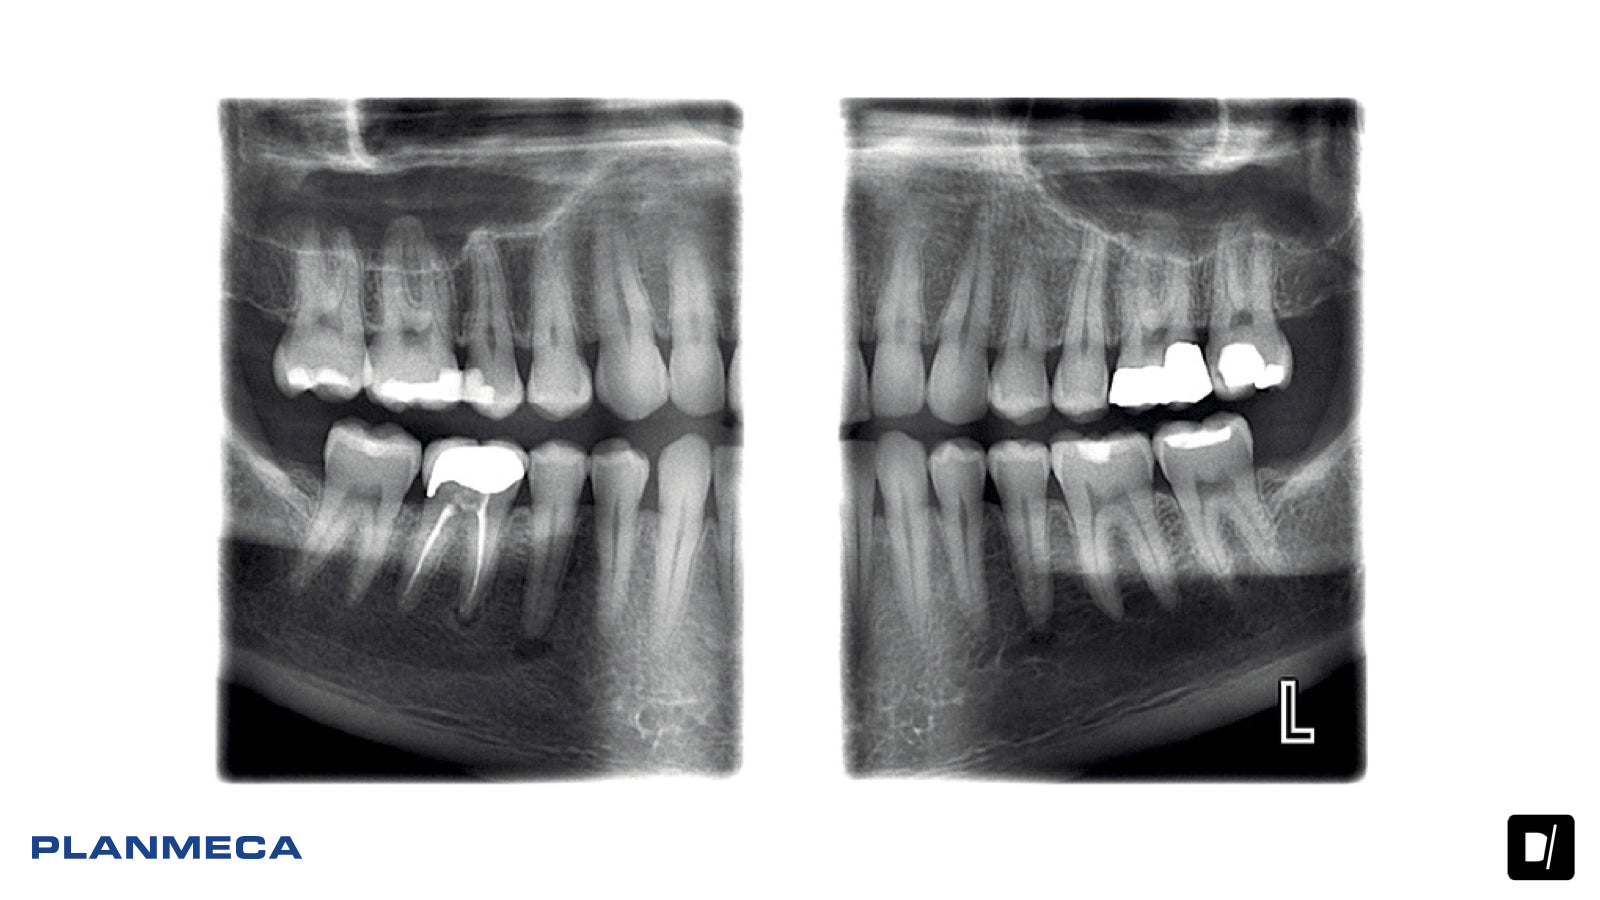

Las unidades de procesamiento de imágenes panorámicas Planmeca ofrecen una avanzada y versátil experiencia de imágenes 2D. Desde el posicionamiento flexible del paciente hasta las innovaciones creativas y la alta calidad de la imagen, representan las imágenes dentales 2D en su máxima expresión.

Las unidades Planmeca ProMax 2D ofrecen la más amplia variedad de programas de procesamiento de imágenes. Se encuentran disponibles distintos programas de imágenes panorámicas, así como opciones para imágenes de ATM, senos y tomográficas. Las unidades también tienen un modo para niños que permite obtener imágenes a dosis más bajas al reducir el área de procesamiento de imágenes y los valores de exposición.

Nuestra tecnología patentada SCARA (Selectively Compliant Articulated Robot Arm / Brazo Robot Articulado Selectivamente Adaptable) garantiza una geometría de imágenes anatómicamente precisa, lo cual genera imágenes claras y sin errores. Con Control de Exposición Dinámico (DEC), las unidades miden la transparencia de radiación del paciente y ajustan automáticamente los valores de exposición.